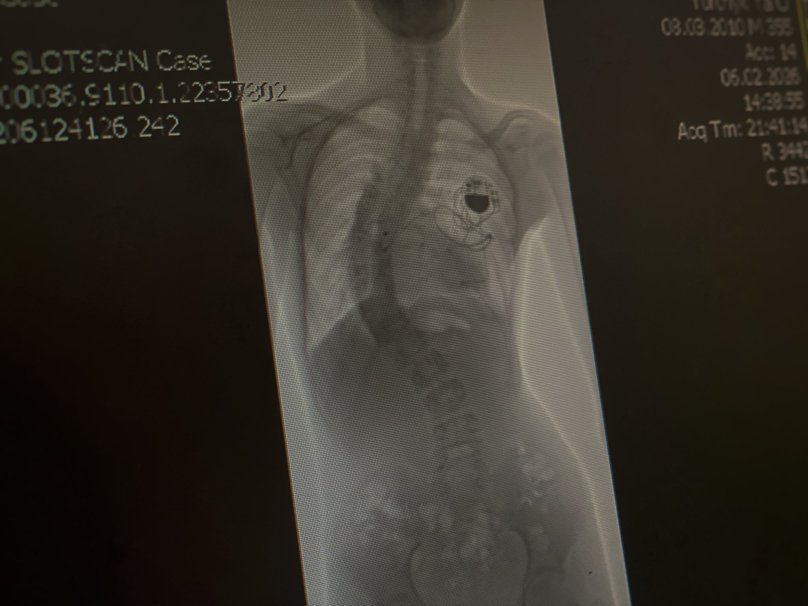

У дитячій лікарні Святого Миколая львівські медики разом з міжнародною командою на чолі з американським хірургом прооперували 16-річного підлітка зі сколіозом найважчого ступеня. Змалечку хлопець живе з кардіостимулятором, тож операцію з виправлення хребта було проводити ризиковано. Однак втручання пройшло успішно і викривлення хребта вдалося зменшити з критичних 80° до 25°. Про це повідомили у Першому ТМО 20 березня.

Ярослав з Львівщини народився з кількома важкими вадами серця і вже в перші дні життя переніс складну операцію. У шестимісячному віці йому встановили кардіостимулятор, який підтримує правильний серцевий ритм.

“Допомогти хлопцю могла лише операція на хребті. Однак кардіостимулятор робив це втручання вкрай ризикованим. Річ у тому, що під час таких операцій при розрізі мʼяких тканин лікарі використовують спеціальне обладнання, що дозволяє уникнути втрати крові. Інструмент подає струм через все тіло дитини та може призвести до збою налаштувань кардіостимулятора і порушення ритму серця”, — розповіли у лікарні.

До операції залучили міжнародну команду на чолі із провідним хірургом зі США Ізадором Ліберманом. Це була їхня перша медична місія до України і Львова. Разом з місцевими лікарями вони провели консультації з кардіологами, переналаштували кардіостимулятор, залучили реаніматологів та нейрофізіолога для постійного моніторингу стану хлопця під час втручання.

Операцію проводили у кілька етапів. Спершу лікарі обережно відокремили спинний мозок Ярослава від навколишніх тканин. За словами медиків, це був один із найнебезпечніших моментів. Далі встановили металеву конструкцію зі стрижнів і гвинтів, яка дозволила вирівняти хребет.

“У результаті викривлення вдалося зменшити з критичних 80° до 25° — це максимально можливий для безпеки спинного мозку показник. А завдяки ретельній підготовці вдалося уникнути кардіологічних ускладнень”, — додали медики.